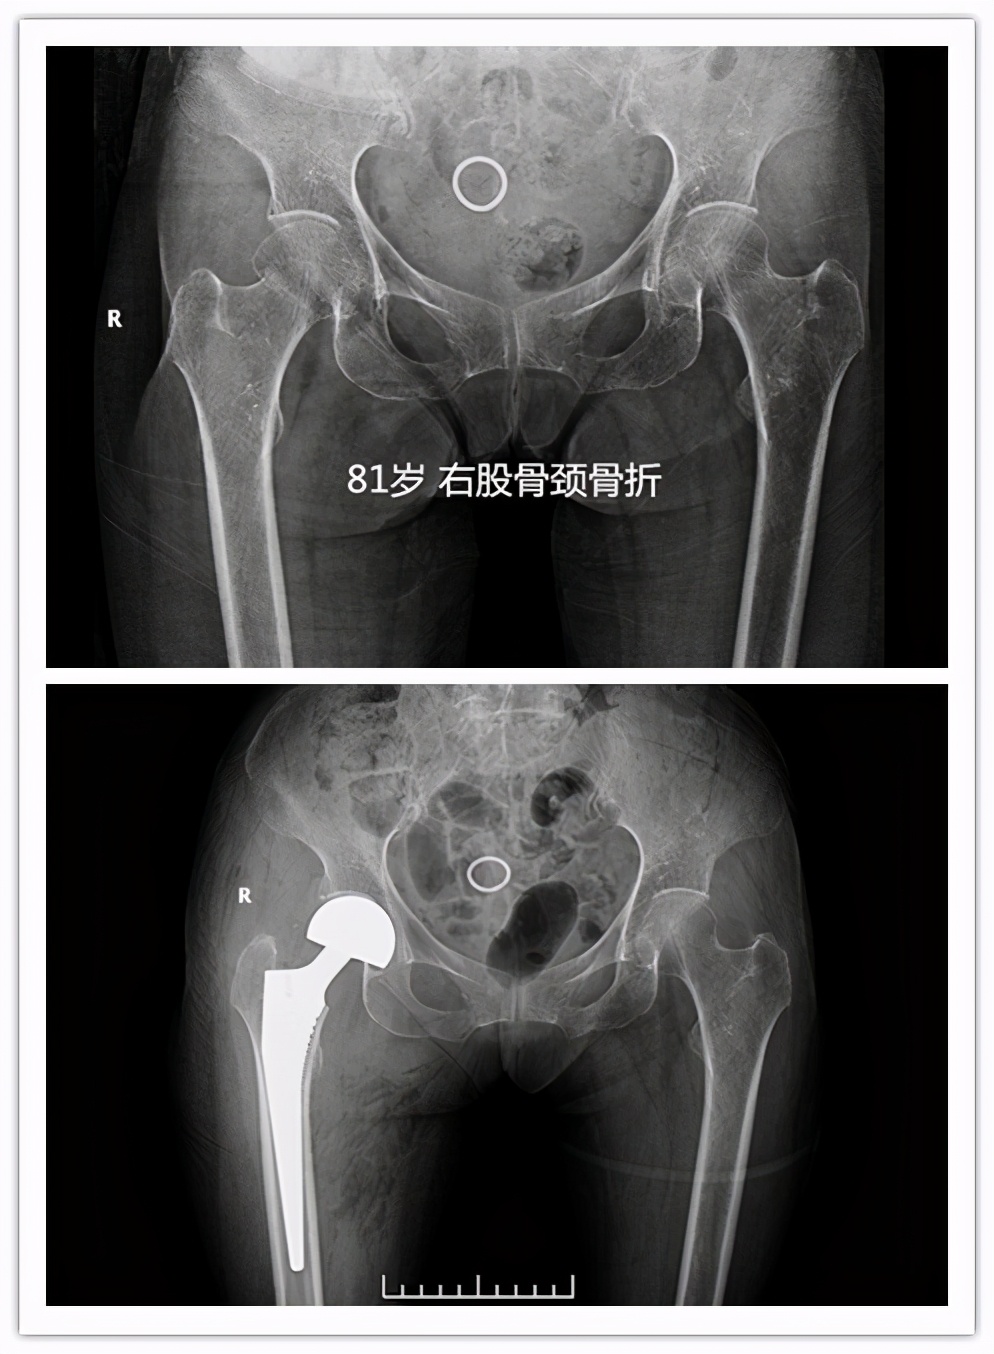

答案就是指 老年人髋部骨折 ,也就是东北话常说的“ 胯骨轴摔坏了 ”,包括股骨颈及粗隆间骨折。这个部位骨折后病人因轻微活动便会诱发较剧烈的疼痛,通常无法坐起、翻身困难,需长期卧床,只有一少部分骨折无移位或者骨折断端嵌插的病人,经2-3个月的卧床后出现骨折愈合后可能恢复行走功能,其余病人可能因骨折不愈合、畸形愈合等丧失行走功能。长期卧床面临着肺内感染、坠积性肺炎、褥疮、下肢静脉血栓、泌尿系感染等并发症, 据统计约50%的患者因卧床出现相关并发症在1年内死亡 ,所以被称作“人生最后一次骨折”。

这种骨折出现了怎么治疗呢?其治疗方法分为手术内固定治疗(如空心钉、PFNA、INTER- tan等等)或者人工关节置换手术治疗。

- 对于老年高龄的股骨颈骨折患者,一般可能人工股骨头置换手术,手术时间短,术后1-2日病人可早期下床活动,降低卧床并发症,提高患者生活治疗。对于粗隆间骨折,可行PFNA或者人工股骨头置换手术。

很多家属最大疑问:我们家的老人都七八十岁了,还能做手术吗?其实跌倒后出现髋部骨折多大出现于老年高龄患者,近两年我们科室做的因股骨颈骨折行人工股骨头置换手术最大年龄为 99岁 ,老人家术后2日扶助行器下床活动。 所以老人是否能耐受手术,不能只看年龄 ,需要请医师进一步进行术前评估。通过手术治疗,病人可尽早离开床,尽快恢复日常生活,提高患者生活质量,降低死亡率。